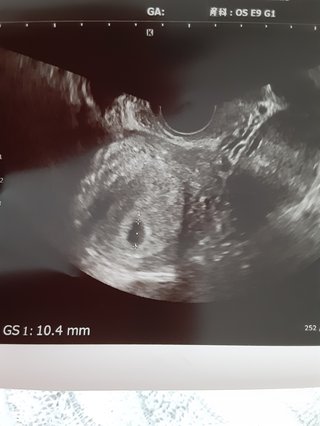

5w5dのエコーで聞きたいです。 投稿画像

5w5dのエコーで聞きたいです。